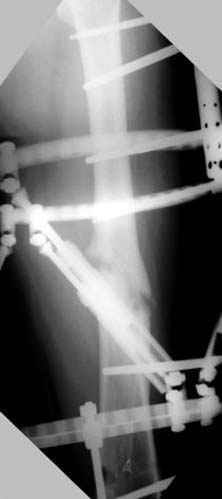

Отправитель: Djoldas Kuldjanov 23 Ноябрь 2004, 18:21

пластическая модель; и коррекция бедра аппаратом Илизарова.

Отправитель: Evgueny Tschekashkin 24 Ноябрь 2004, 21:09

хотя даже если бы и инфекция , то nail exchange с рассверливанием канала - вариант дебрайдмента) Я думаю, что последовательность развития событий:

Узкий к-м канал - тонкий гвоздь- усталостный перелом дистальных винтов - развитие нестабильности и как ее результат остеолиз вокруг гвоздя - деформация анатомической оси бедра. Похоже, что я понял почему аппарат, а не новый гвоздь:-)

ЕТ - Изначально костно-мозговой канал бедра был узкий, дальнейшее его рассверливание ещё больше скомпрометирует прочность бедра( латеральный кортекс дистального отломка уже истончен), приведет к дефекту наружной стенки - хотя это только мои догадки - хотелось бы знать мнение Джолдаса о выбранной тактике.